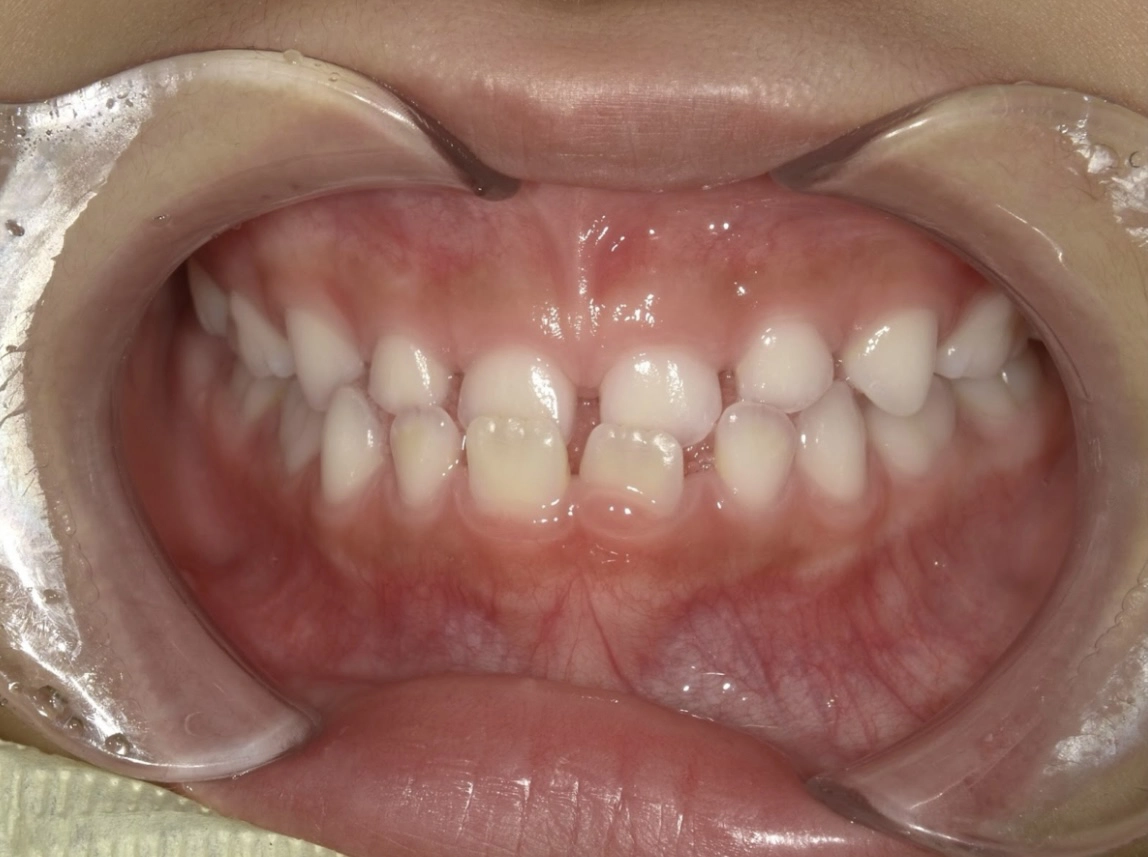

治療前

治療後

| 術名 | 小児矯正の症例 |

|---|---|

| 年齢 | 7歳 |

| 性別 | 女児 |

| 主訴 | 下の歯が出ているのが気になる |

| 診断名 | 前歯部反対咬合 |

| 治療内容 | プレオルソ |

| 治療期間 | 12ヶ月 |

| 費用 | 6万+税 ※別途月々の調整料(5500円)がかかります |

| リスク・副作用 | ご自身で着脱していただくマウスピースなので、使用時間が短いと十分な効果が得られません |